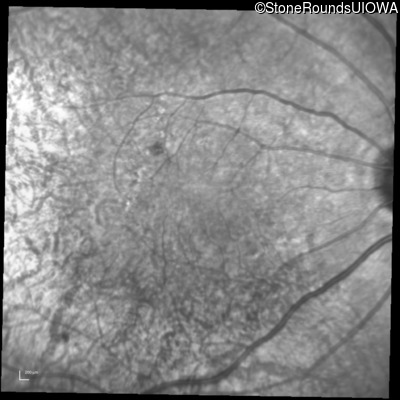

Infrared Fundus Photograph - Left - 20/30 -2

Exemplar